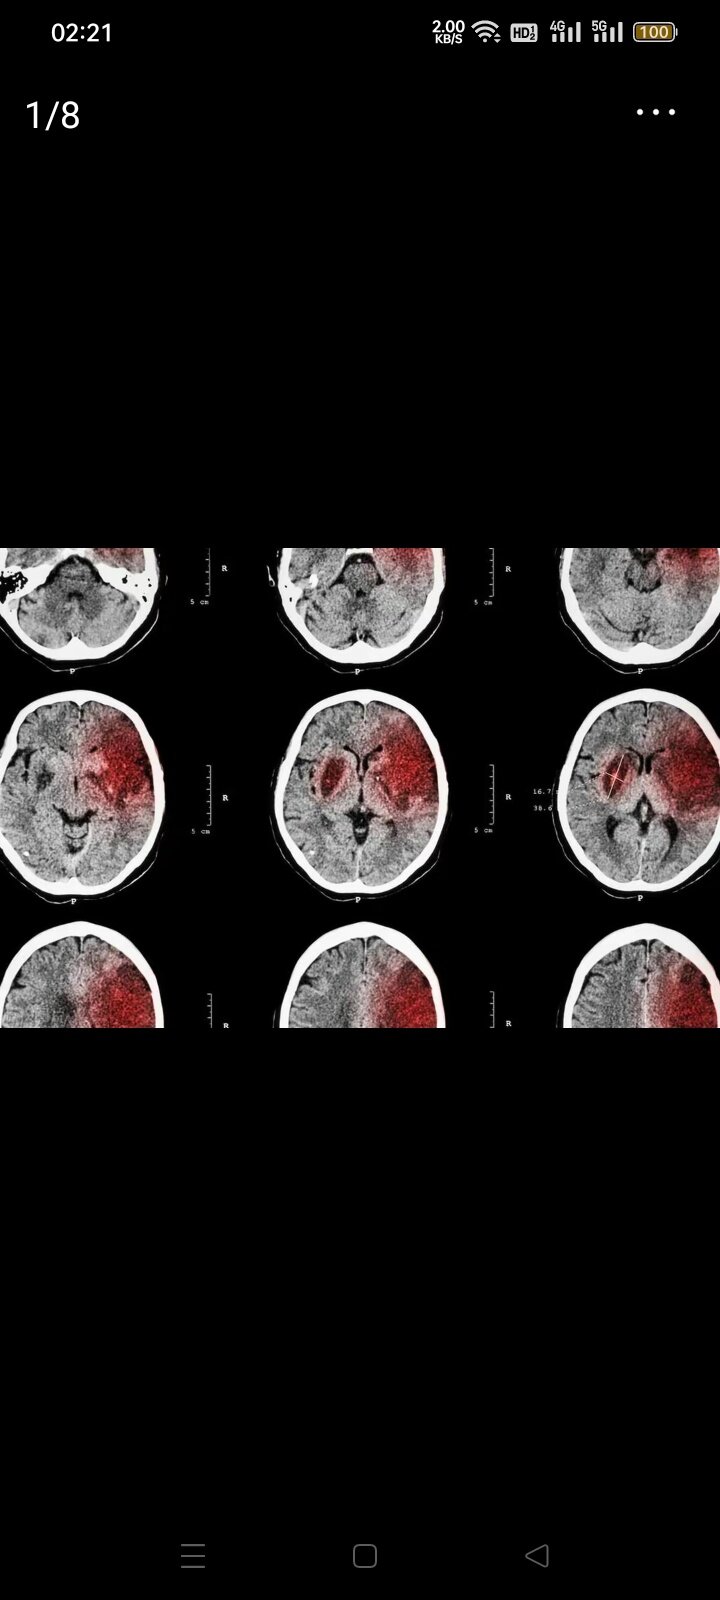

说句不好的 晚期

患者估计是老年人吧,如果以前有过癌症病史,影响结论显示是扩散到咽喉,淋巴和肺

考虑癌症并且有转移

应该是肺癌晚期,我爸爸去年检查出来的结果跟你这个差不多,跑了三个医院结果都一样确诊肺癌晚期。恶性肿瘤,转移,钙化,结节

癌症了撒,考虑是让你做进一步检查,要确诊的话要做活检

就是做了活检,结果还没有出来,医生说大概率是咽喉或者食道晚期,请问还有必要去重庆检查吗?

核检还没有出来,他现在是喉咙痛吞东西吞不下去,不知道是哪种,就是看不懂报告,家里说再去重庆检查,请问还有必要吗?